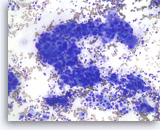

Ductal adenocarcinoma #1,

Pancreas FNA, Cell Block.

The tumor cells are pleomorphic and form poorly organized glands of variable sizes. Some of the glands are fused together. Prominent intracytoplasmic mucin is present.

40X

Ductal adenocarcinoma #1,

Pancreas FNA, Cell Block.

The tumor cells are pleomorphic and form poorly organized glands of variable sizes. Some of the glands are fused together. Prominent intracytoplasmic mucin is present.

40X